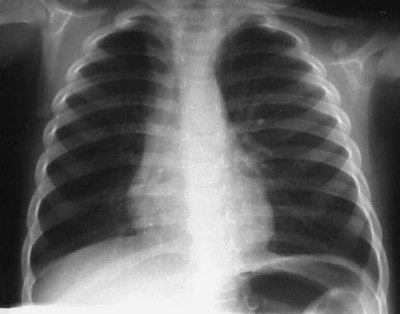

In figure 6 we have a 24-month-old who has been intubated, with a diagnosis of RSV. The film is slightly overpenetrated as we cannot clearly make out lung markings, but we can see the bronchial air shadow and the tip of the ETT (marker arrow), which is right at the carina (the bifurcation of the right and left mainstem bronchus). Doctors attempted to re-position the ETT and the left lung is ruptured causing a tension pneumothorax (arrow, figure 7).

In figure 8, the radiographic technique has been adjusted to show lung markings after the placement of a chest tube on the left. The chest tube, however, appears to be abutting the ETT, and notice the air shadow extending around the pericardium and along the diaphragm, consistent with the diagnoses of pneumomediastinum.